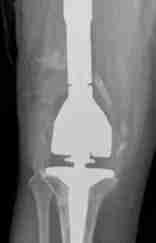

Cirugía de Revisión Total de Reemplazo de Rodilla

Aflojamiento e Desgaste del Implante

A veces el implante puede aflojarse.

No siempre está claro qué puede llevar a un implante suelto.

Los cirujanos ortopédicos creen que las actividades repetitivas de alto impacto, el alto peso corporal y el desgaste del revestimiento de plástico pueden llevar a un desgaste más rápido de su reemplazo de rodilla, lo que lleva al aflojamiento del implante.

Los pacientes que se someten a un reemplazo de rodilla a una edad más joven tienen un alto riesgo de que su reemplazo de rodilla se afloje.

El aflojamiento ocurre cuando las diminutas partículas generadas cuando el revestimiento de plástico se desgasta son atacadas por el sistema inmunológico de su cuerpo.

El sistema inmunológico luego destruye el hueso sano alrededor del implante.

Esta destrucción ósea se llama “osteólisis”.

Cuando ocurre la osteólisis, los implantes pueden comenzar a tener un movimiento de limpiaparabrisas y aflojarse, causando dolor.

Fracturas

Las fracturas (hueso roto) suelen ocurrir después de una caída o una osteólisis severa.

El Dr. Morton evaluará la fractura alrededor de su rodilla investigando el hueso restante, el aflojamiento del implante y la ubicación de la fractura.

La mayoría de las fracturas requieren cirugía para corregirlas.

En algunos casos, solo se requiere un período de carga protegida, sin cirugía.

Preparación para la Cirugía

Una revisión total de rodilla requiere una preparación extensa.

El Dr. Morton necesitará sus historiales médicos anteriores, radiografías y otras imágenes.

A veces, antes de la cirugía, ordenará imágenes más avanzadas como una tomografía computarizada (CT) o una resonancia magnética (MRI).